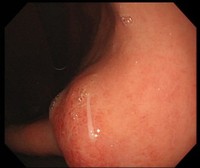

治療の第一選択は、内視鏡による摘出ですが、内視鏡は必要ないとの報告もあります。アレルギーを抑える注射と香蘇散という漢方薬で、ほとんどのアニサキス症を治療できるとの報告を見たことがあります。ただ、私は、万全を期すため一般的な内視鏡による摘出を第一選択としたいと思っています。